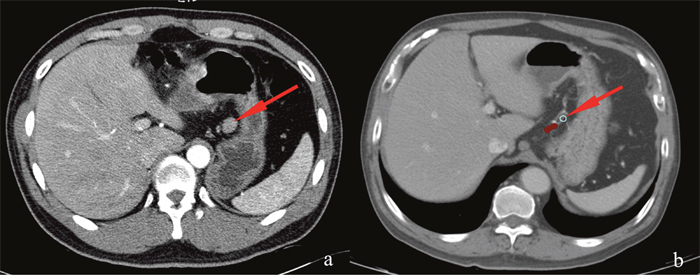

Secondly, we drew the 2846 LNcs on the Monaco® version 5.0 workstation. Figure 3 showed the delineation process. The basic principles were as follows. (a) We depicted the contour of the LNc at the equivalent location on the axial views of CT images compared with that in the GC patient by measuring the distance from the lymph node to landmarks such as the vascular structure, the gastric wall, the pancreas and the spleen. (b) A circle with a diameter of 5 mm was used to replace the central position of the metastatic LN to avoid the mass effect of enlarged LNs. This process is also suitable when metastasis LNs invade the vessels or the adjacent structure. (c) When the nodes mixed together, we drew the LNc of each node that was distinguishable in its respective location. Otherwise, we drew the LNc of their geometric central position. A consensus committee of three physicians, two radiologists with a gastrointestinal specialty and one radiation oncologist with three years of work experience agreed on this process.

Figure 3: Delineation of LNc in the standard patient. (a) An enlarged lymph node (arrow) located in the lesser curvature in a 33-year-old male gastric cancer patient. (b) A circle with a diameter of 5 mm (arrow) was used to replace the center of the enlarged lymph node at an equivalent location based on the relative distances to the same reference vessels and the gastric wall of the standard patient.